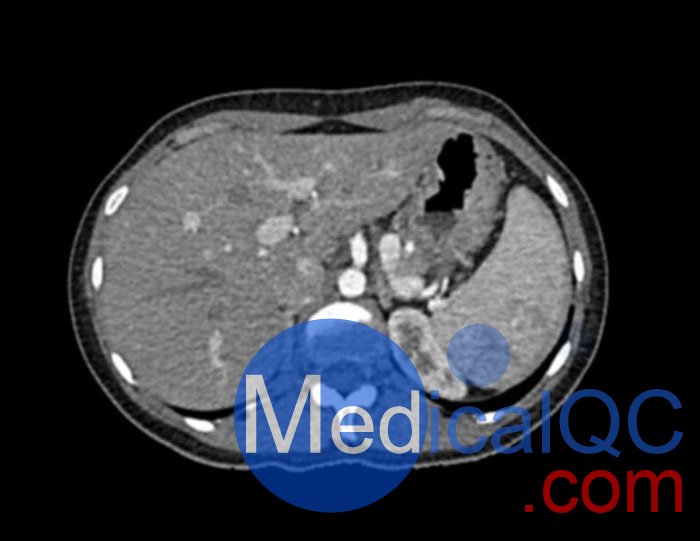

WEK53-01腹部模體,WEK53-01動脈期腹部模體,WEK53-01腹部模型模擬了動脈期的造影劑增強腹部。它覆蓋了第十一胸椎至第四腰椎(部分包括在內)。

該模型可用于 CT(包括 CBCT)以評估和優化成像性能和后處理應用,包括支持 AI 的應用。它也適用于培訓目的。

該模型提供了對軟組織和骨組織的詳細而逼真的模擬。空隙中填充著約-160HU的纖維素-聚合物復合材料。